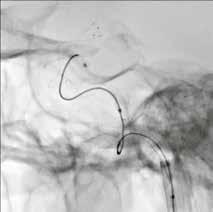

Die Alphenix Angiographiesysteme von Canon Medical können nun mit innovativer HD-Technologie ausgestattet werden. Mit dem weltweit ersten hochauflösenden Flachdetektor für die Angiographie sind kleinste Gefäße und Gefäßanomalien mit kleinsten interventionellen Devices besser behandelbar. Im Interview spricht Matthias Schmidbauer, Manager Sales Support X-Ray bei Canon Medical Systems, über die Vorteile der neuartigen HD-Technologie für neurovaskuläre Eingriffe.

Diese neuartige Technologie ist das Ergebnis jahrelanger Forschungsarbeit, die wir in Zusammenarbeit mit führenden Kliniken, wie dem Gates Vascular Institute in Buffalo, geleistet haben. Es ist uns gelungen, den weltweit ersten hochauflösenden Flachdetektor für die dynamische Bildgebung in der Angiographie zur Marktreife zu führen. Die Auflösung des HD-Flachdetektors konnten wir auf außergewöhnliche

6,5 Linienpaare pro Millimeter steigern –

auf einen ca. doppelt so hohen Wert, verglichen mit konventionellen Systemen. Um jetzt auf Ihre Frage zurückzukommen, können damit kleinste Gefäße und Gefäßanomalien mit

kleinsten interventionellen Devices sicherer und schneller behandelt werden, was diese Technologie insbesondere für die Behandlung zerebraler Gefäßerkrankungen prädestiniert.

Standard-Flachdetektor

Wenn Neuroradiologen beispielsweise intrakranielle Aneurysmen mit dem endovaskulären Coiling-Verfahren behandeln, benötigen sie Sichtkontakt zur Läsion. Je besser sie die feinen, über einen Mikrokatheter in das Aneurysma vorgeschobenen Platinspiralen, die sogenannten Coils, sehen, desto präziser

HD-Flachdetektor

und zügiger können sie diese im Aneurysma packen und dessen Innenwand abdecken. Häufig muss die entfaltete Platinspirale zusätzlich noch durch einen Stent mit sehr feinem Drahtgeflecht gestützt werden, der ebenfalls genau zu platzieren ist.

Durch die Vergrößerungsmöglichkeit im HD-Modus können diese kleinen

Devices und Gefäßstrukturen auf dem Monitor klar dargestellt werden. Somit ist auch der Behandlungsfortschritt genauer nachvollziehbar. Der HDFlachdetektor funktioniert in diesem Zusammenhang wie ein Mikroskop für den Neuroradiologen. Es leuchtet ein, dass die HD-Technologie daher zu besseren Behandlungsergebnissen und höheren Überlebensraten führt.

Klinischer Fall: 11 mm Kavernöses Karotisaneurysma rechts; Behandlung mit LVIS-Blue-Stent und Coils; Bildgebung mit lateralem HD-Flachdetektor, 6 cm x 6 cm FOV, Fluoro-Modus.

Bildgebung mit Standard- und HD-Flachdetektor.